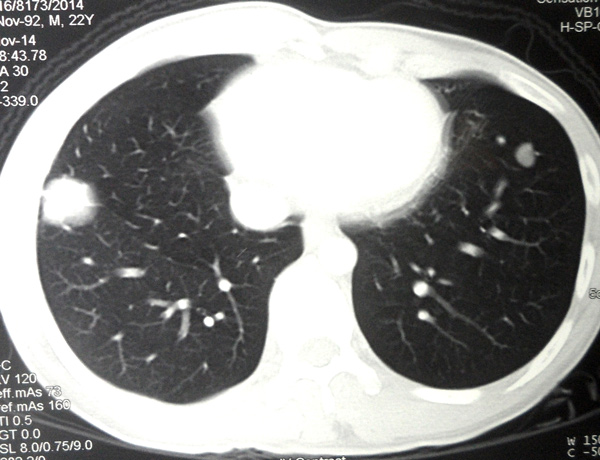

A CT scan on 30 October 2013 showed:

- An irregular lesion in the right lung apex, 35 x 42 x 28 mm.

- Speckles of calcification in both lungs upper lobe suggesting prior tuberculous infection.

- Bilateral supraclavicular lymph node 10 to 20 mm.

- Multiple enlarged mediastinal and right hilar lymph nodes.

- Numerous small nodules in both lungs – likely metastases.